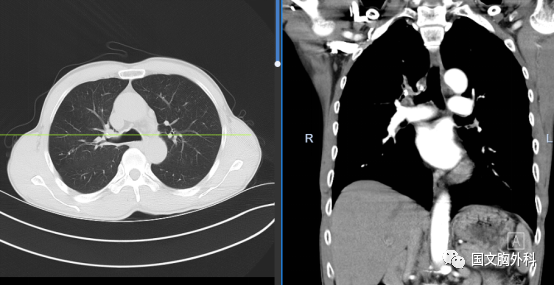

周大爺,發(fā)現(xiàn)肺占位1個月。CT下觀察右肺上葉腫物延續(xù)至肺門,穿刺病理提示:肺鱗癌。有手術(shù)機會,家屬同意手術(shù)治療。

術(shù)中患者右肺門分離困難,決定行右肺上葉袖型切除,在長達8小時的奮斗后,周大爺手術(shù)順利結(jié)束。